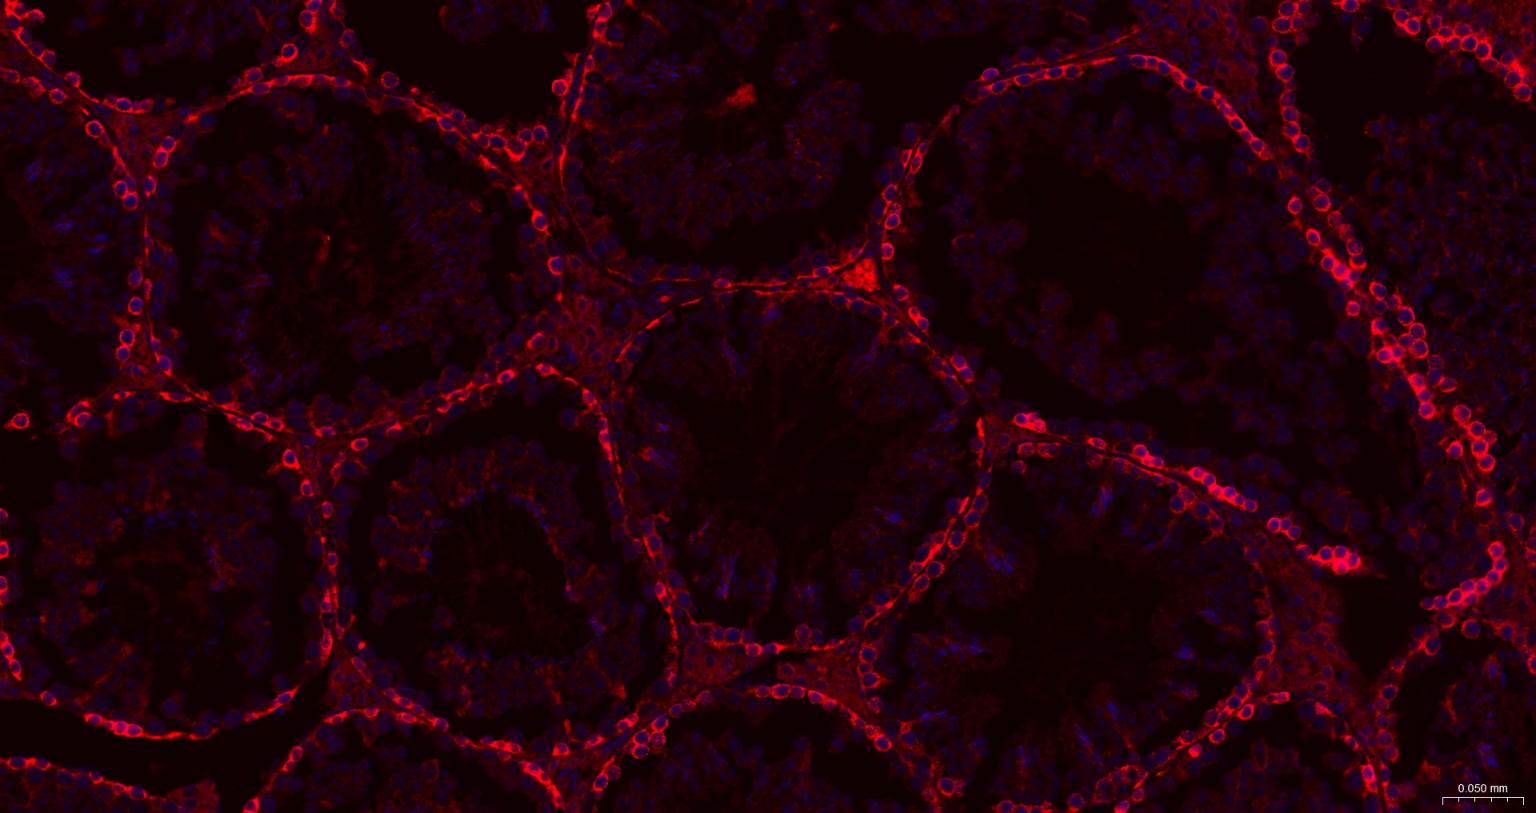

| IF | Human, Mouse, Rat | 1:100-500 | |

| ICC/IF | Human, Mouse, Rat | 1:50-200 |